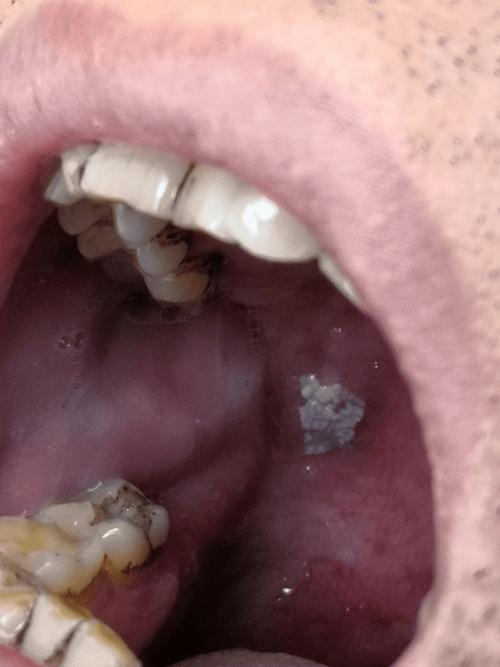

扁平苔藓 (Lichen Planus)

一种原因不明的慢性炎症性皮肤黏膜病。

- 外观:

- 典型表现为“网状”或“花纹状”的白色条纹(称为Wickham纹),可以呈灰色或蓝色。

- 这些条纹可以相互交叉,形成网状图案,常见于颊黏膜、舌、牙龈等处。

- 有时也会出现白色丘疹或斑块。